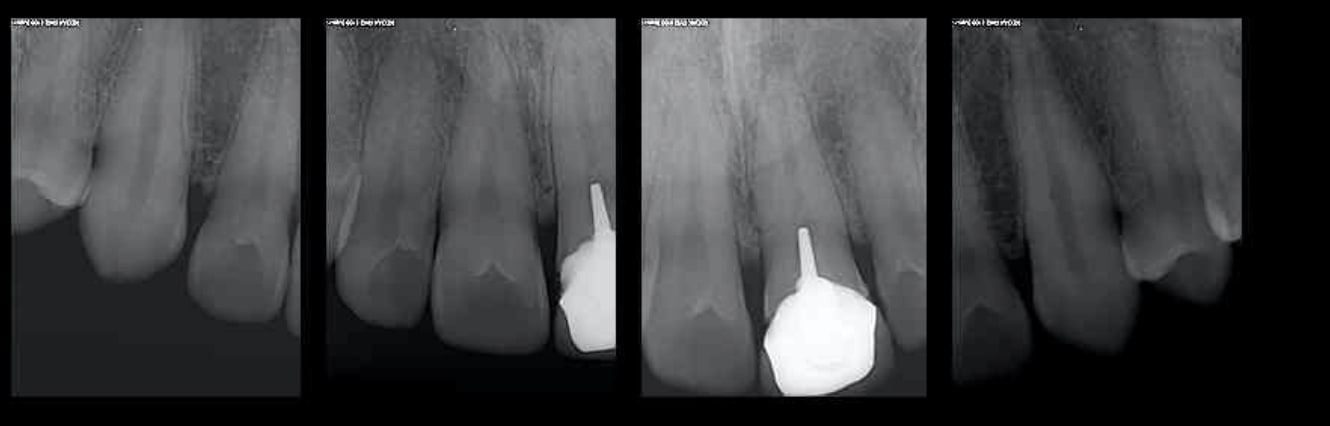

Tiens 13 instruments endo pour faire le RTE ci dessus. Il y en a pour combien à votre avis si on les jette à chaque fois ? Et c'est pareil pour des bio pulpectomies. Donc oui c'est une tromperie de faire croire que pour 100 balles les endos tarif sécu sont réalisées conformément aux données actuelles de la science.